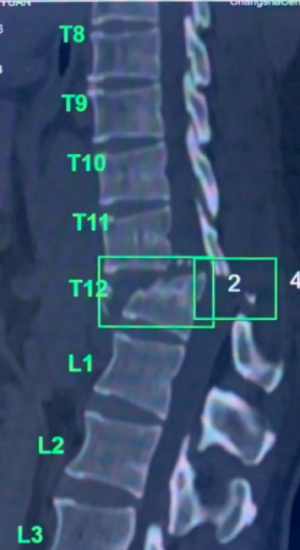

(南华大学附属长沙中心医院)急诊科,CT和磁共振检查提示胸腰段T11、T12椎体爆裂性骨折并脱位,并脊髓损伤伴截瘫,这是脊柱脊髓损伤中最严重的情况。

术前检查示胸腰段T11、T12椎体爆裂性骨折并脱位